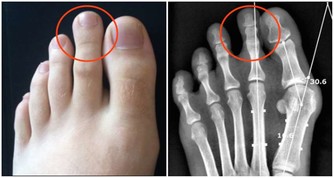

想要判定痛風患者能不能吃魚肉,就要看魚肉是不是含有高嘌呤物質。魚的種類有很多種,像一些沙丁魚、鳳尾魚、小乾魚等這類含有高嘌呤物質,建議痛風患者最好不要食用。